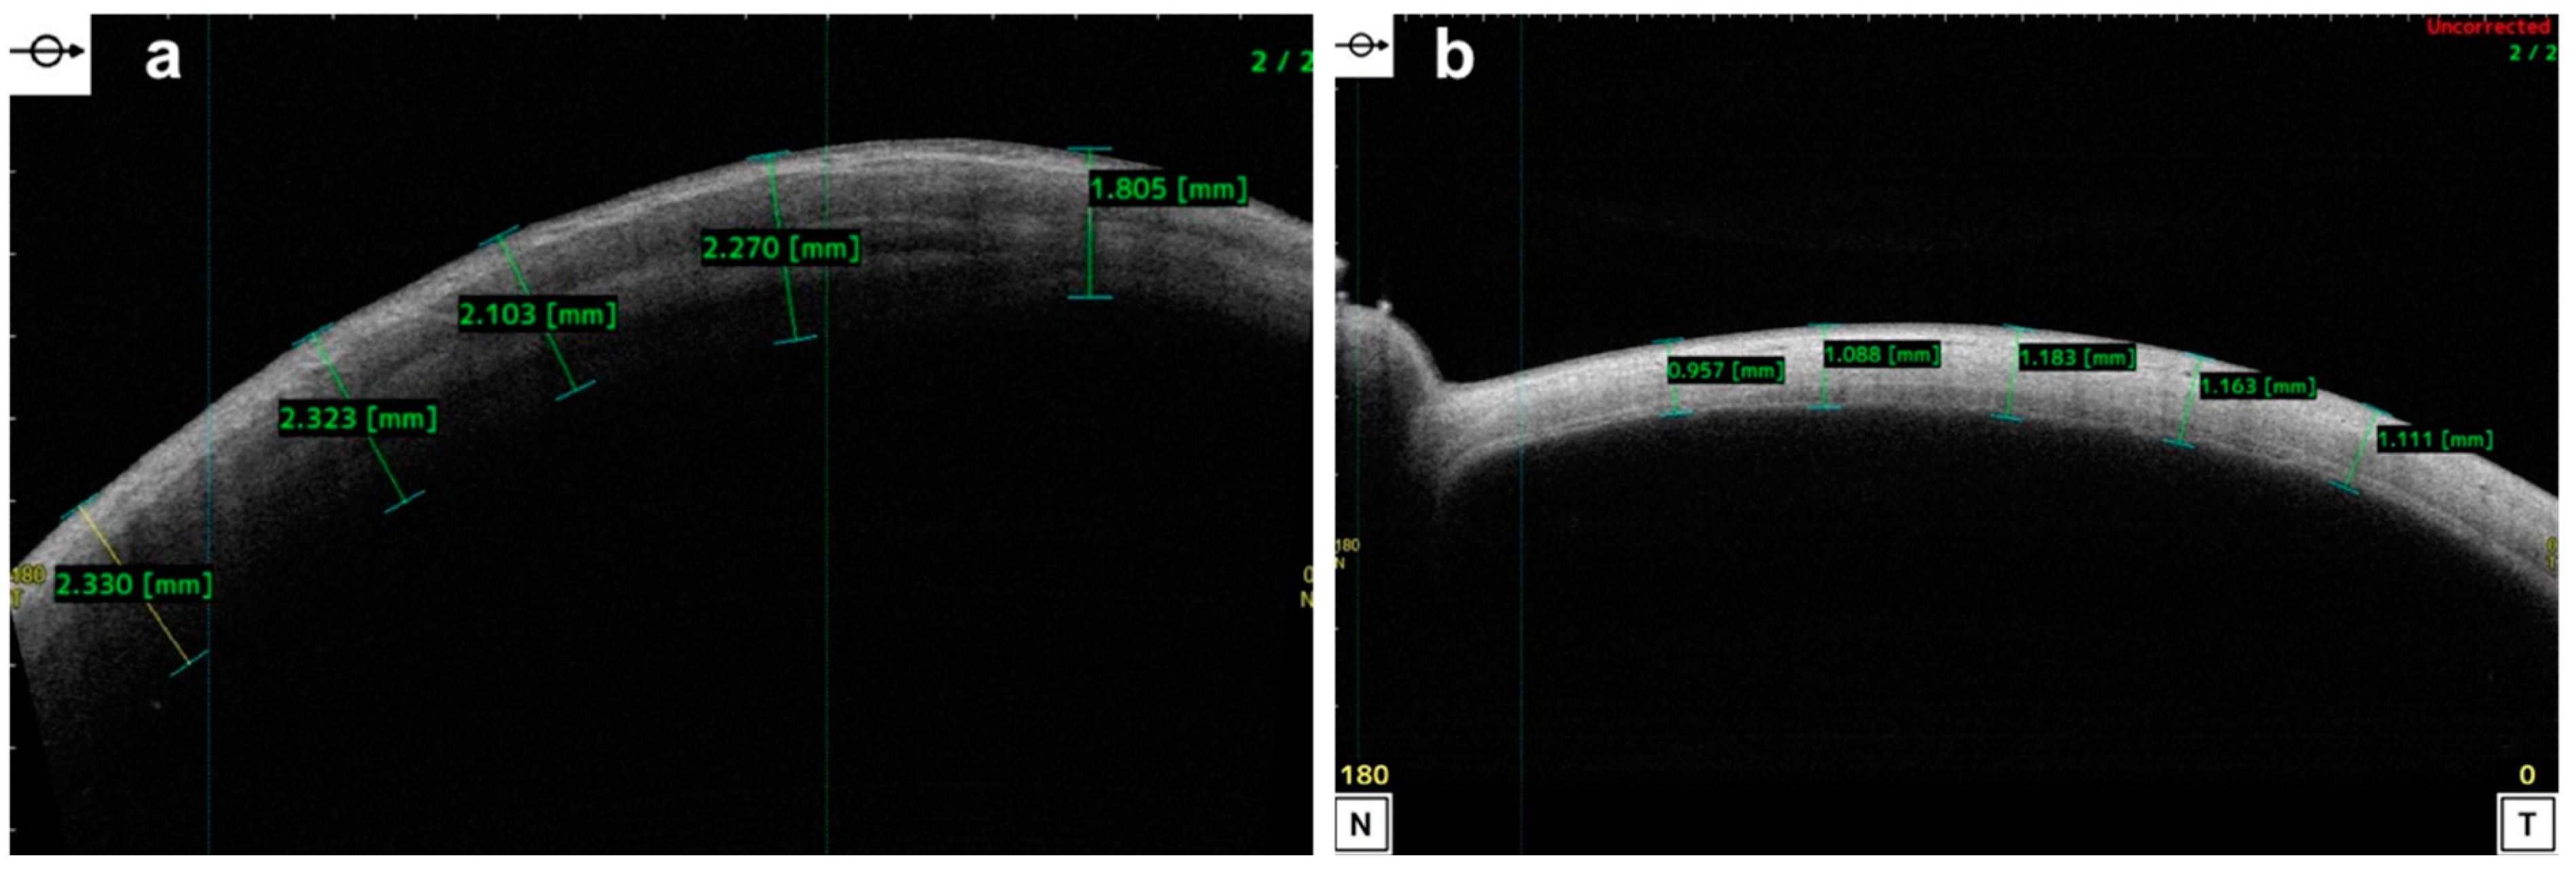

6.5. Epithelial Thickness Mapping in Corneal Disease

7. Clinical Applications in Corneal and Refractive Surgeries